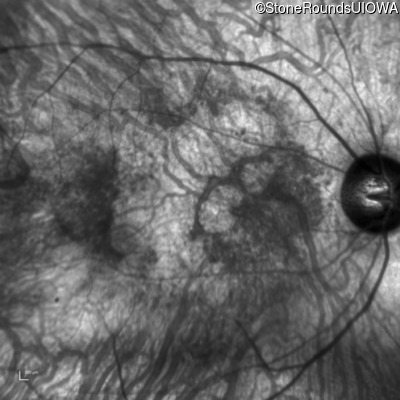

Infrared Fundus Photograph - Right - 20/200 +2

Exemplar